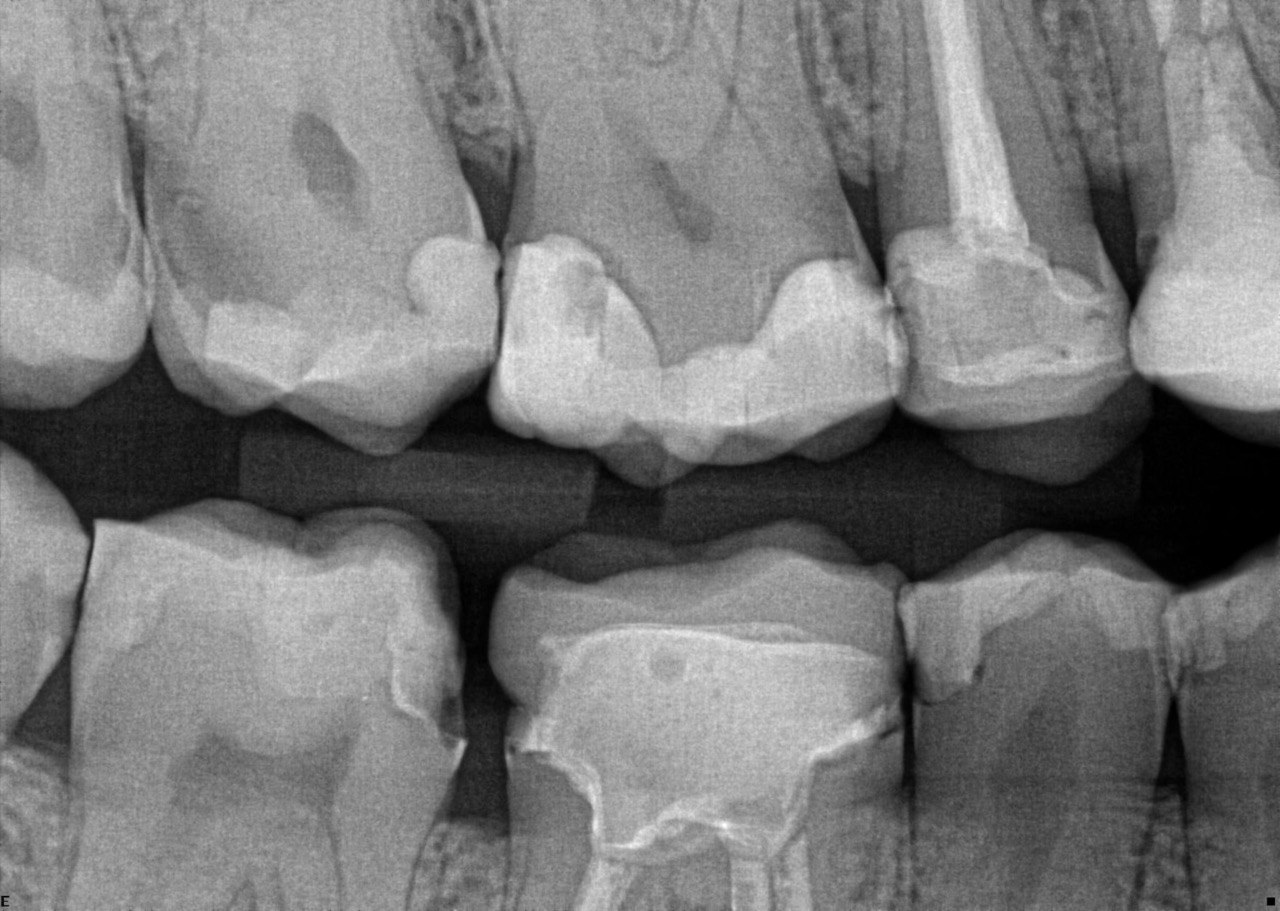

Question 1: What is the condition of the mesial surface of the tooth # 2.6?

Question 2. What is the condition of the mesial of the tooth # 2.7?

Question 3. What is the condition of the distal surface of the tooth # 2.7 and mesial surface of the tooth # 2.8 respectively?

Question 4: what is the condition of the distal of the tooth # 4.1 and mesial of the tooth #3.1 respectively?